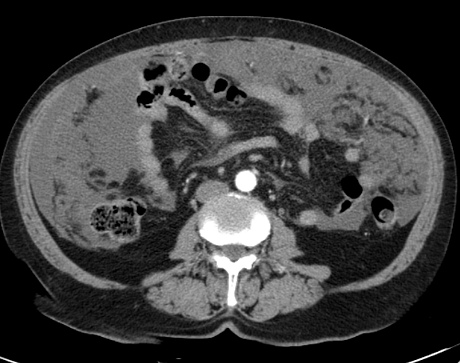

Дополнительно специалисты отправляют пациента на лабораторные анализы. По их результатам можно определить количество лейкоцитов, уровень СОЭ, гемоглобина. Лабораторные исследования в обязательном порядке дополняются инструментальной диагностикой. Она включает в себя УЗИ, компьютерную, магнитно-резонансную томографию. Наиболее информативной методикой считается лапароскопия. В ходе ее осуществляется изучение внутренних органов с дальнейшей биопсией.